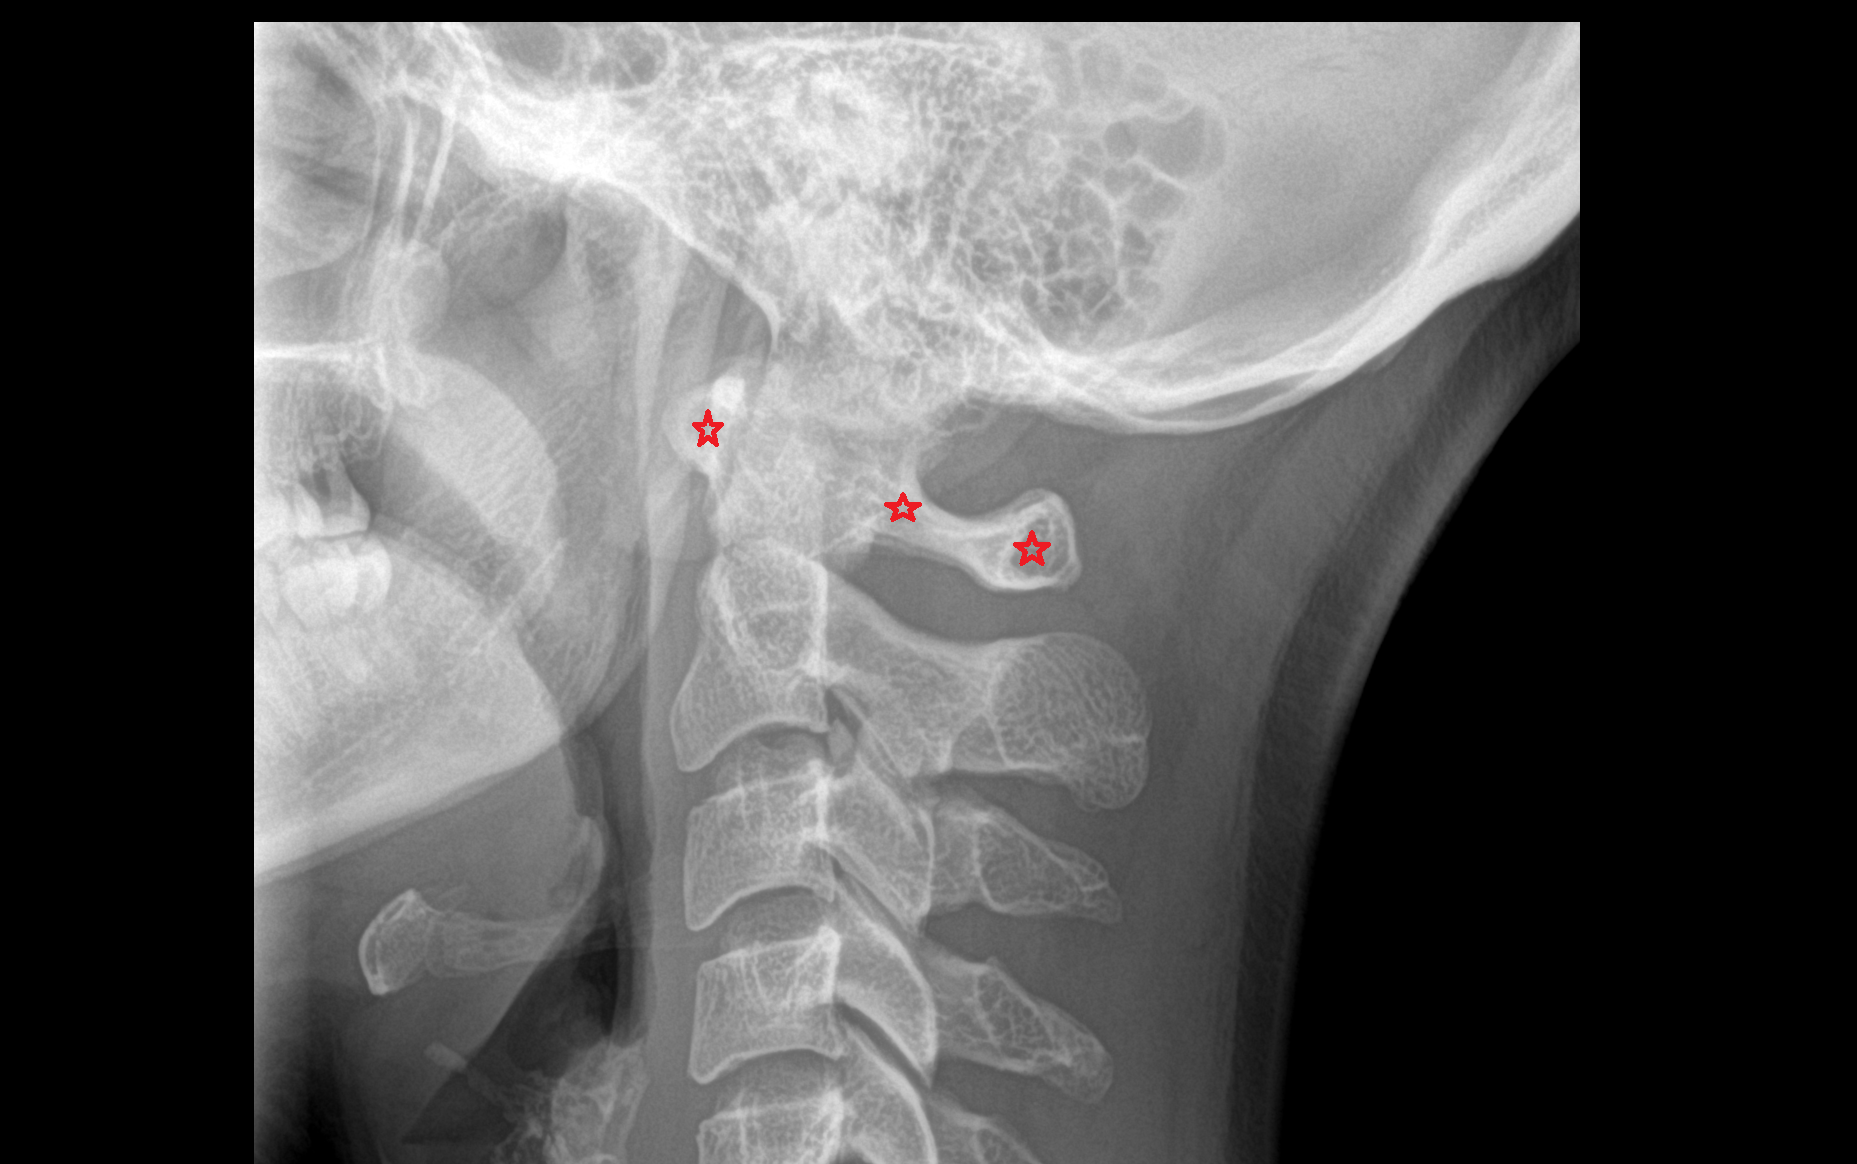

- Axis (C2 vertebra)

- Dens of axis

- Atlantooccipital joint

- Lateral atlantoaxial joint

- Median atlantoaxial joint